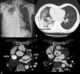

Occlusion of pulmonary vein

An embolism is the lodging of an embolus, a blockage-causing piece of material, inside a blood vessel. The embolus may be a blood clot (thrombus), a fat globule (fat embolism), a bubble of air or other gas (gas embolism), amniotic fluid (amniotic fluid embolism), or foreign material. [Source: Wikipedia ]